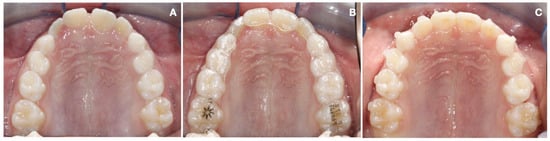

2.1. Treatment Protocol